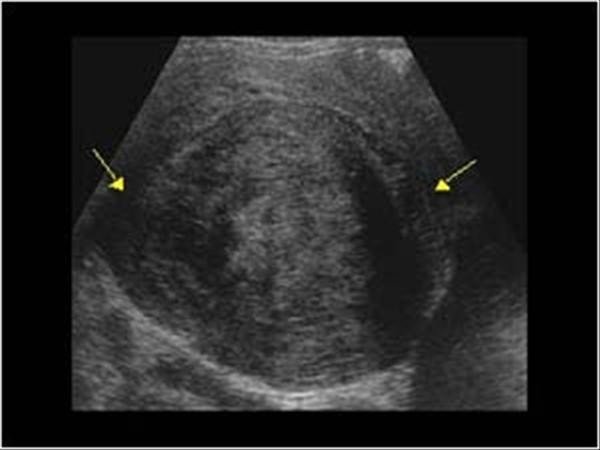

Miyomların genellikle ihmal edildiğine dikkat çeken Kadın Hastalıkları ve Doğum Uzmanı Prof. Dr. Selahattin Kumru, en sık görülen kadın hastalığı olan miyomların tedavisinin kolay olduğunu, tedavi edilmemesi durumunda ise büyük boyutlara ulaşabileceğini ifade etti. Kumru, kanama, kasık ağrısı, kısırlık ve gebelik kaybına neden olabilen, miyom gibi görünen bazı rahim tümörlerinin nadir de olsa kanser hücresi taşıyabileceğini belirtti.

Her 3 kadından 1'inde görülen miyomların en sık rahim tümörü olduğunun altını çizen Kumru, tam olarak neden ortaya çıktığının hala tartışmalı olduğunu ancak genellikle iyi huylu tümörler olduğunu vurguladı. Miyom görünümünde olup içerisinde kötü hücre barındıran (kötü huylu/kanser) olguların oldukça nadir karşılaşıldığını belirten Kumru, yine de takip sırasında hızlı büyüyen miyom görünümlü kitlelerde kanser açısından dikkatli olunması gerektiği konusunda uyardı.

Prof. Dr. Selahattin Kumru, sürekli kasık ağrısı çeken, karında şişlik, adet kanamasının süresinde ya da miktarında artma, ara kanamalar, sık idrara çıkma, kabızlık, cinsel aktivite sırasında ağrı gibi şikayetleri olan kadınların, mutlaka jinekolojik muayene ve ultrasonogafi ile değerlendirilmeleri gerektiğini hatırlattı. Prof. Dr. Kumru, "Halk arasında ultrasonografik olarak miyomu olan olgularda anormal aşırı kanamaların nedeninin genellikle miyomlara bağlandığını, oysa hem miyomların bir kısmının gerçekte miyom görünümlü kanserler olması hem de miyomlar ile birlikte rahim içinde kalınlaşma (endometrial hiperplazi) olması, miyomu olan olguların dikkatli değerlendirilmesini zorunlu kıldığını ifade etti. İhmal edilmiş durumlarda geç kalma ve kanser ise ileri evrelere dönüşme riski mevcuttur" dedi.

Prof. Dr. Kumru şöyle devam etti: "Örneğin rahimin içine doğru büyüyen miyomlar düzensiz kanamalar, gebe kalmakta zorluklar ve düşük (gebelik kaybı) gibi sorunlara neden olurken dışarıya doğru büyüyen miyomlar sessizce kalabilirler ve tesadüfen fark edebilirler. Rahmin ön tarafında bulunan idrar torbasına baskı yapan miyomlar sık sık idrara çıkma ve önde baskı hissine neden olurken arka taraftaki bağırsağa doğru baskı yapan miyomlar dışkılama zorluğu, kabızlık, cinsel ilişki sırasında ağrı gibi şikayetlere neden olabilirler. Yine miyomlar büyüdükçe karında şişlik ve ağrıya neden olabilmektedirler. Bazı hastalar rahim büyüdüğü için karınlarında meydana gelen şişlikleri kilo aldıklarını düşünerek ihmal ederler ve doktora başvurmakta geç kalırlar. Miyomlar nedeniyle aşırı büyümüş rahimler, kalpten çıkan kanın önemli bir kısmı rahime gitmek zorunda olduğu için çabuk yorulma halsizlik, efor kapasitesinde azalma gibi sorunlar da yaşamaktadırlar."